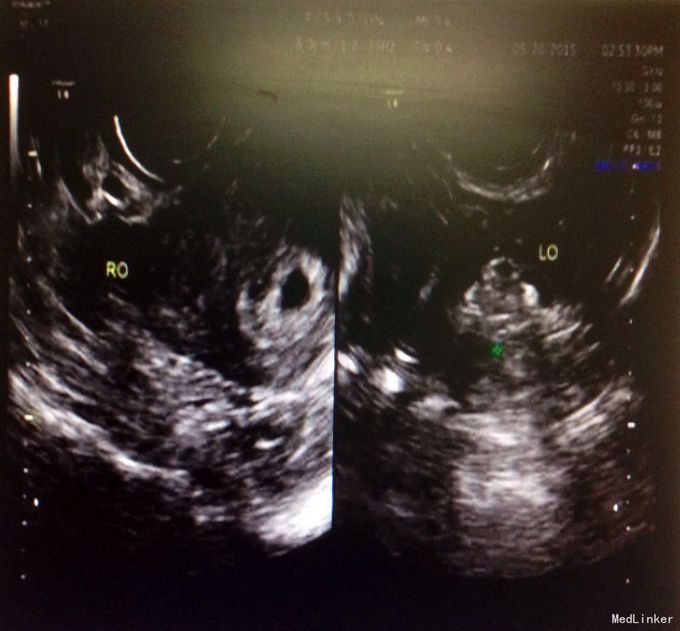

主诉:ET术后27天,呕吐1周 现病史:患者平素月经规律,5/28,27天前因“继发不孕”于我院行ET术,移植冻胚2个,1周前出现恶心、呕吐,呕吐呈喷射性,呕吐物为胃内容物,有胃部烧灼感,进食即吐,未予特殊治疗,门诊收入院。

体检:生命体征正常,无压痛及反跳痛,肝脾肋下未及,肾区叩痛(-),移动性浊音(-),双下肢无浮肿,未行内诊。 辅助检查:B超及生化相关检查如图

入院诊断:早孕,ET术后,妊娠剧吐 诊疗经过:入院后予营养补液支持治疗,达芙通口服黄体酮注射保胎治疗,复查血电解质尿常规正常后出院。